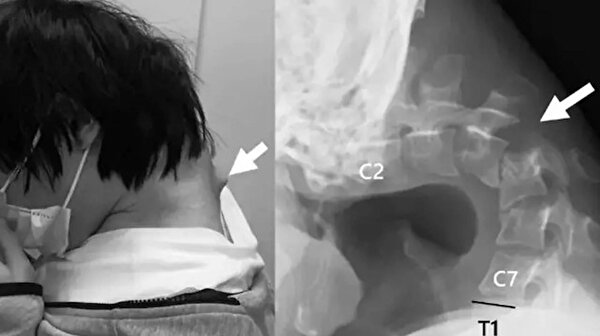

Bir MRI taraması, başının uzun süre doğal olmayan bir pozisyonda olmasının yıkıcı etkilerini gösterdi. Servikal omurgası hasarlıydı, pozisyonu bozuktu ve aşırı gerilmeden dolayı yara dokusu vardı. Omurgasında ciddi hasar ve deformasyon tespit edilirken, boyun kaslarının işlevini yitirdiği belirlendi.

25 yaşındaki adama, sürekli telefonuna bakması nedeniyle başını kaldıramamaya başlaması üzerine Düşük Kafa Sendromu teşhisi konuldu.

Doktorlar, elle müdahale ve atel kullanımının yetersiz kalması üzerine cerrahi operasyona karar verdi.

Vida ve metal çubuklar yerleştirildi

Operasyonda hasarlı omurlar ve dokular çıkarılıp, boynu hizalamak için vida ve metal çubuklar yerleştirildi. Ameliyattan altı ay sonra hasta başını kaldırmaya başladı, bir yıl içinde ise hareket kabiliyeti ve duruşunda belirgin iyileşme gözlendi. Doktorlar, genç yaşta ortaya çıkan bu vakanın nadir olduğunu belirtirken, “Düşük Kafa Sendromu”nun akıllı telefon ve tablet kullanımına bağlı olduğunu vurguladı.